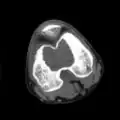

Other imaging techniques involve computed tomography (CT), magnetic resonance imaging (MRI), and bone scans, which may be helpful in determining the anatomical boundaries, associated edema, or biological activity of the chondroblastoma, respectively.[8][10] MRI studies may show extensive oedema around the lesion and show variable T2 signal intensity.[15]

1. b. CT scan shows chondroblastoma of thigh bone near knee more clearly